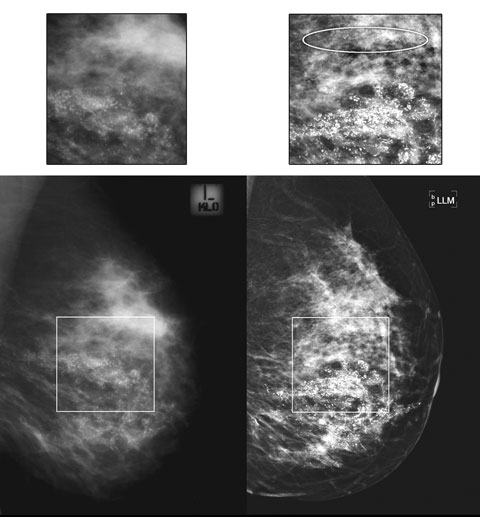

Evidence is also accumulating in radiological literature that DM is superior to CM for demonstration of microcalcifications.9-11 Box 6 demonstrates the example of a woman referred for HNL and wide local excision of DCIS, where DM showed a more extensive distribution of malignant calcifications, thus necessitating a change in management to mastectomy.